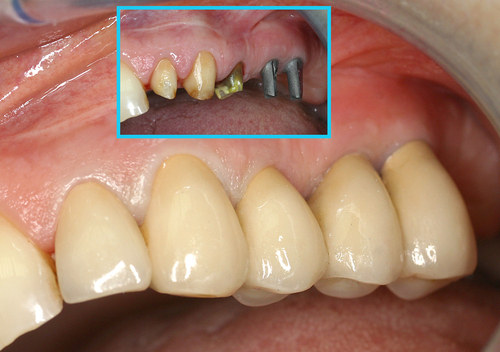

Ce volume osseux obtenu permet facilement la mise en place d’implants en remplacement des molaires absentes et la mise en place d’une prothèse fixe fonctionnelle et esthétique (fig.32)

Fig. 32

Mise en place des implants et prothèse finale